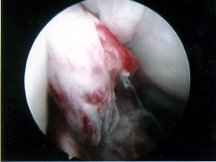

ACL Rupture

Exclude combined ACL+ Meniscal Detachment

• Osteohondral fracture: Lipo-haemarthrosis